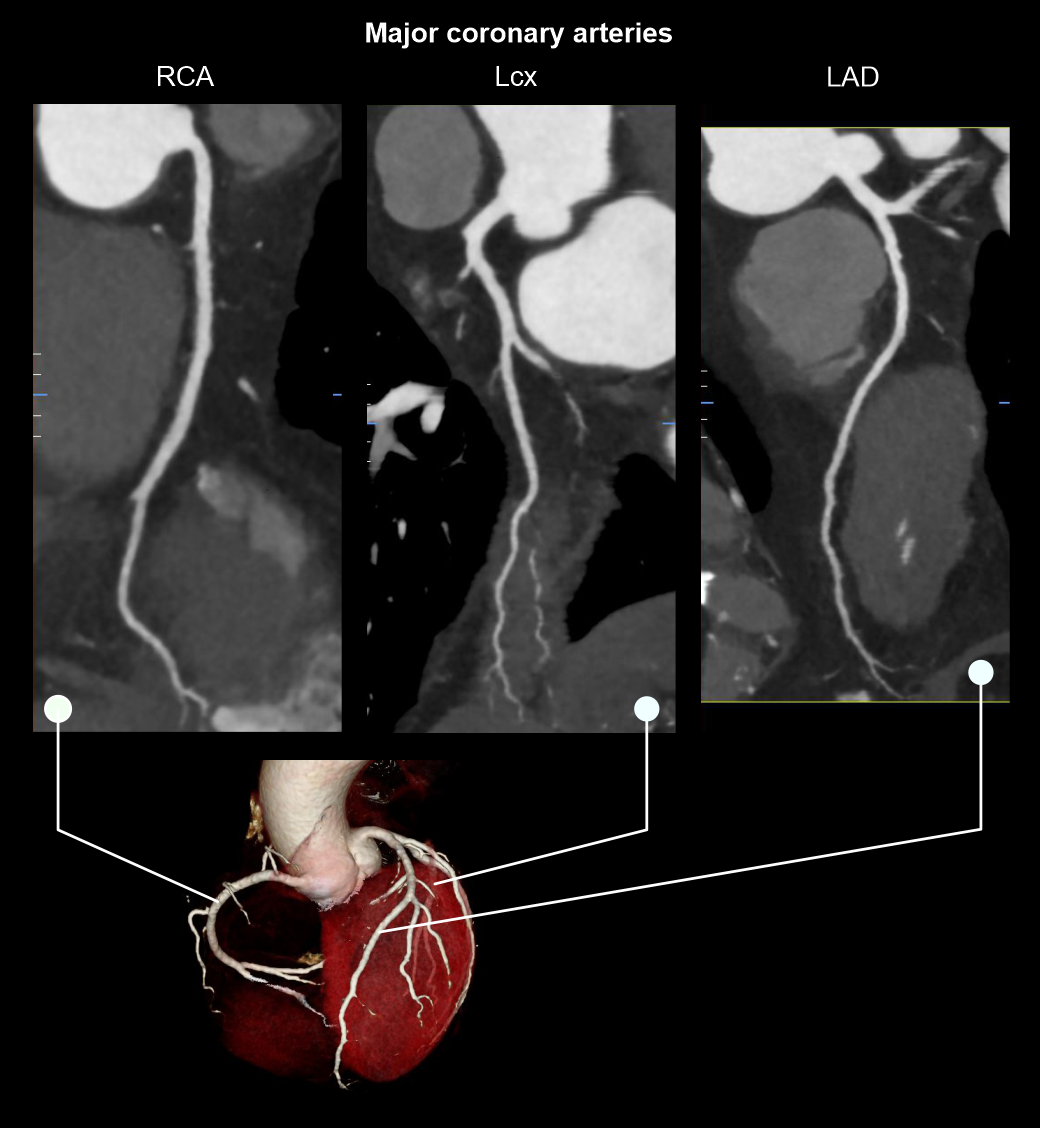

SitemapHeadNCCT BrainCECT BrainSinusesOrbitsInner ear (IAM)CisternographyCerebral angiographyCerebral VenographyNeckNCCT NeckCECT NeckCarotid angiography4D neckChestNCCT ChestCECT ChestHRCT ChestCoronary Calcium ScoringCoronary angiographyPulmonary angiographyThoracic aortogramAbdomenNCCT AbdomenMultiphase CE AbdomenNCCT KUBUrography (IVU)Renal AngiographyMesenteric AngiographyAbdominal AortogramColonographyAdrenal protocolSpineCervical spineThoracic spineLumbar spineFull spineMyelographyUpper LimbShoulder jointElbow jointWrist jointHandLower LimbHip jointKnee jointAnkle jointFootPeripheral angiography